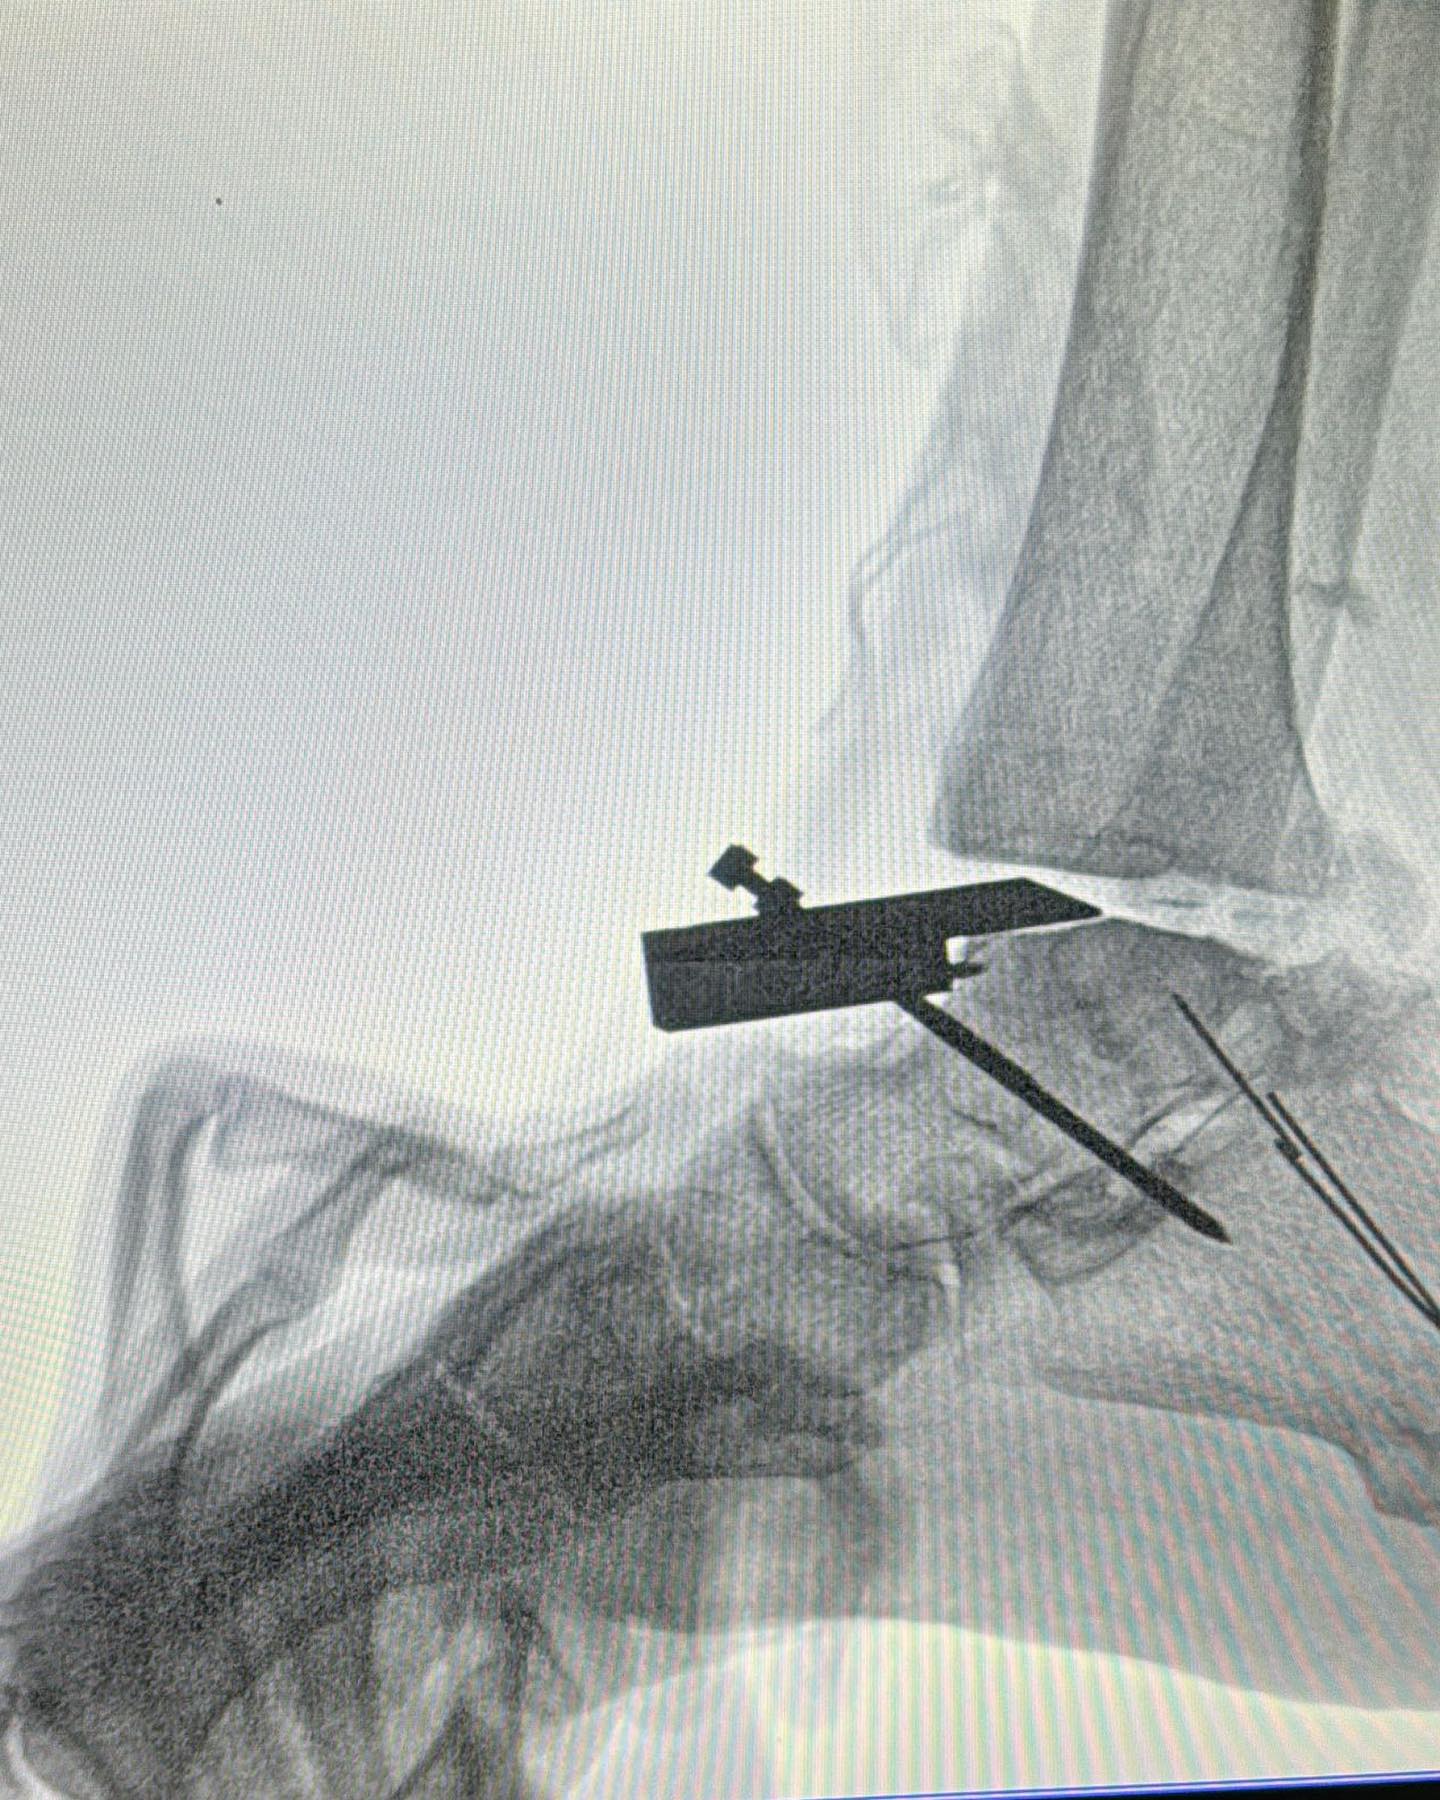

Este procedimiento quirúrgico consiste en sustituir la articulación dañada por una prótesis compuesta de metal y plástico, diseñada para restaurar la movilidad y aliviar el dolor.